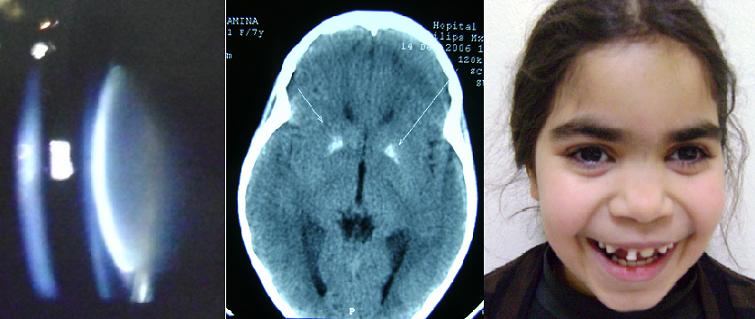

Fillette âgée de 09 ans, issue d’un mariage consanguin de 1er degré, consultait pour une baisse d’acuité visuelle bilatérale d’installation progressive. L’examen ophtalmologique trouvait une cataracte corticonucléaire et sous capsulaire postérieure bilatérale. L’examen général a objectivé un retard staturo-pondéral à moins 3DS avec une mauvaise dentition. Les examens paracliniques ont montré une hyporparathyroïdie vraie, associée à des calcifications des noyaux gris centraux à la TDM cérébrale, et un retard d’âge osseux. La patiente a bénéficié d’une phacophagie, capsulotomie postérieure, vitrectomie antérieure et implantation dans le sac au niveau des 2 yeux. L’évolution est favorable avec une acuité à 10/10. Le traitement étiologique consiste à un traitement substitutif à base de calcium et alphacalcitriol. L’hyporparathyroïdie est une étiologie rare des cataractes métaboliques chez l’enfant. L’hypocalcémie prolongée joue un rôle cataractogène déterminant. Les manifestations ophtalmologiques sont rarement au premier plan. Il ne faut pas se contenter d’un examen ophtalmologique strict devant une cataracte chez l’enfant. Le bilan phosphocalcique doit faire partie de tout bilan étiologique parce que le pronostic vital peut être mis en jeu.